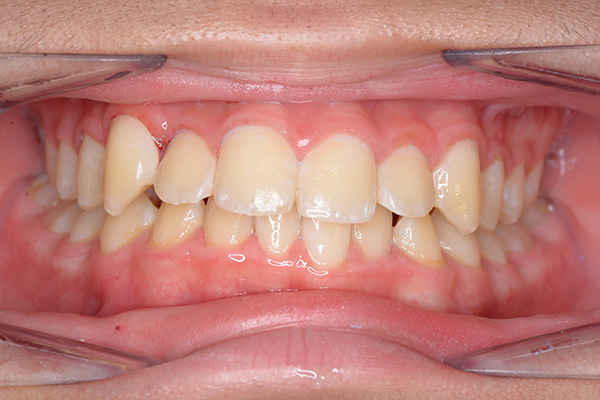

| 口腔内所見 | over jet 5.5mm,over bite 5.0mm,大臼歯関係はⅠ級 、Hellmanのdental ageはⅢBであり上突歯列を呈していた。 |

| セファロ所見 | Sellaに対して下顎頭は後方位だが下顎骨は大きくしっかりとした形態をしており前後的にはⅠ級、垂直的にはロウアングルの骨格形態をしていた。 上顎前歯は唇側傾斜を呈していた。 |

| パノラマ所見 | 上顎左右側犬歯は近心傾斜し側切歯歯根に重なるように認められた。 |

| 批評・予后 | 埋伏歯の牽引を行い位置異常の改善をした結果、適切な犬歯のガイドが得られ、ほぼ緊密な咬合となったように思う。口元の改善を希望された場合は小臼歯抜歯症例として本格矯正治療を行う予定である。 |